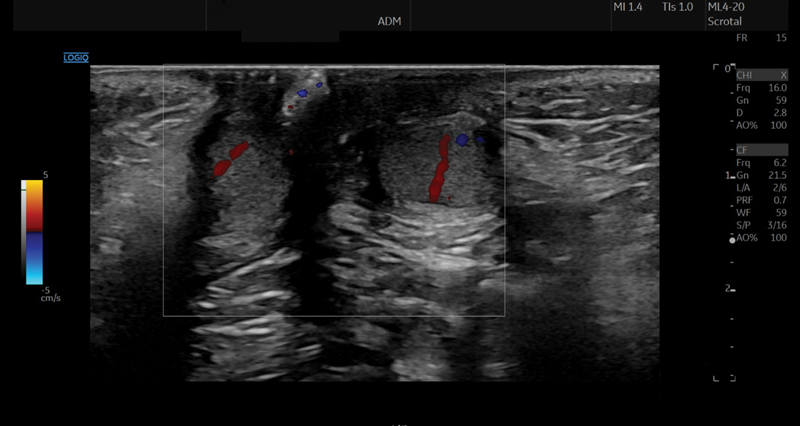

Transverse testicular ectopy (TTE) is a rare anomaly in which both testicles descend through the same inguinal canal. Different variants of this anomaly exist, with the most common presenting as two separate spermatic cords and testicular vessel bundles. The management of this condition is challenging, as various factors have to be considered. We report on a 2-month-old preterm boy with TTE, admitted to the hospital due to an ipsilateral incarcerated inguinal hernia. Diagnostic workup included a physical examination revealing a large swelling in the right groin, ultrasound imaging that showed both testicles located in the right inguinal canal, and laboratory tests indicating a deficiency of anti-Mullerian hormone. All of these findings confirmed the diagnosis of TTE. Surgical treatment included diagnostic laparoscopy with herniorrhaphy, followed by inguinal revision with transseptal orchidopexy in a second procedure. The 12-month follow-up was uneventful. Though rare, TTE is an important differential diagnosis in case of an incarcerated hernia combined with (contralateral) empty scrotum. Pediatric surgeons must be aware of this entity. Meticulous diagnostic workup and careful surgical management are mandatory.